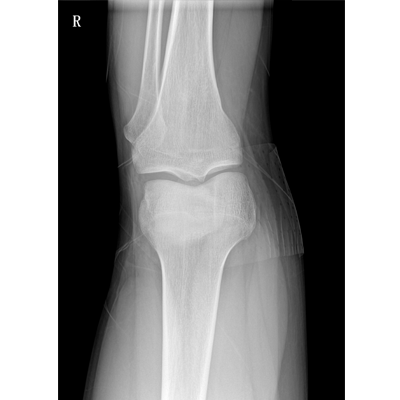

輕量化設(shè)計(jì) 小巧靈活 PLX5100

用于影像科、急診室、病房、ICU、手術(shù)室等多場景應(yīng)用。

● 數(shù)字化無線平板成像,操作簡便,成像質(zhì)量高